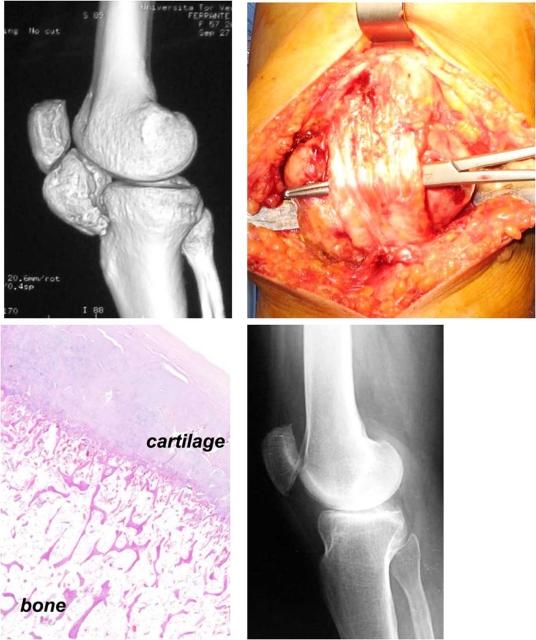

We report two cases of a giant extrasynovial osteochondroma of the knee located in the infrapatellar fat pad region, in two females who were 58 and 71 years old respectively. Both patients had noticed the mass many years before our first clinical observation. In both patients, at physical examination a solid, firm and hard mass was palpable in the anterior part of the knee in Hoffa's fat pad region, and the range of motion of the knee was severely restricted and painful. CT scan examination with 3D-reconstruction showed two large, calcified neoformations behind the patellar tendon, between the apex of the patella and the proximal third of the tibia. In both cases, the mass was completely resected surgically through an anterior longitudinal approach. At histological examination, the excised masses consisted of an outer layer of hyaline cartilage without significant chondrocyte atypia and an inner region of bone trabeculae formed by endochondral ossification. At follow-up, 8 and 4 years after the operation, both patients were pain-free, with complete recovery of the range of motion of the knee and without any clinical or radiographic evidence of recurrence. The authors believe that intra-articular extrasynovial osteochondroma of the knee is a primary metaplasia of Hoffa's fat pad. Usually, the tumor develops slowly and asymptomatically over many years. The treatment of choice is a marginal resection of the mass, although a biopsy should be considered in some cases. Recurrences are extremely rare.

我们报告了两例位于髌下脂肪垫区域的膝关节巨大滑膜外骨软骨瘤病例,患者分别为两名女性,年龄分别为58岁和71岁。两名患者在我们首次临床观察前多年就已注意到肿块。两名患者在体格检查时,均在霍法脂肪垫区域的膝关节前部可触及一个坚实、坚硬的肿块,膝关节活动范围严重受限且疼痛。CT扫描三维重建显示,在髌腱后方、髌骨尖与胫骨近端三分之一之间有两个大的钙化新生物。在这两例病例中,均通过前纵行入路手术完整切除了肿块。组织学检查显示,切除的肿块由一层无明显软骨细胞异型性的透明软骨外层和一个由软骨内成骨形成的骨小梁内部区域组成。随访时,术后8年和4年,两名患者均无疼痛,膝关节活动范围完全恢复,且无任何临床或影像学复发证据。作者认为,膝关节关节内滑膜外骨软骨瘤是霍法脂肪垫的一种原发性化生。通常,肿瘤多年来发展缓慢且无症状。治疗的选择是肿块边缘切除,不过在某些情况下应考虑进行活检。复发极为罕见。